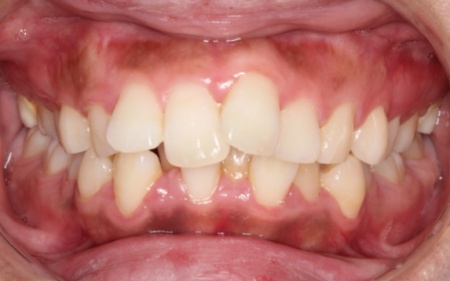

60代女性 すきっ歯が目立つ噛み合わせをワイヤー矯正とアライナー矯正の併用で改善した症例

- 矯正歯科

- ワイヤー矯正

- マウスピース矯正

- 治療期間の目安 1年3ヶ月

- 治療回数の目安 -

- 治療費総額の目安 1,100,000円